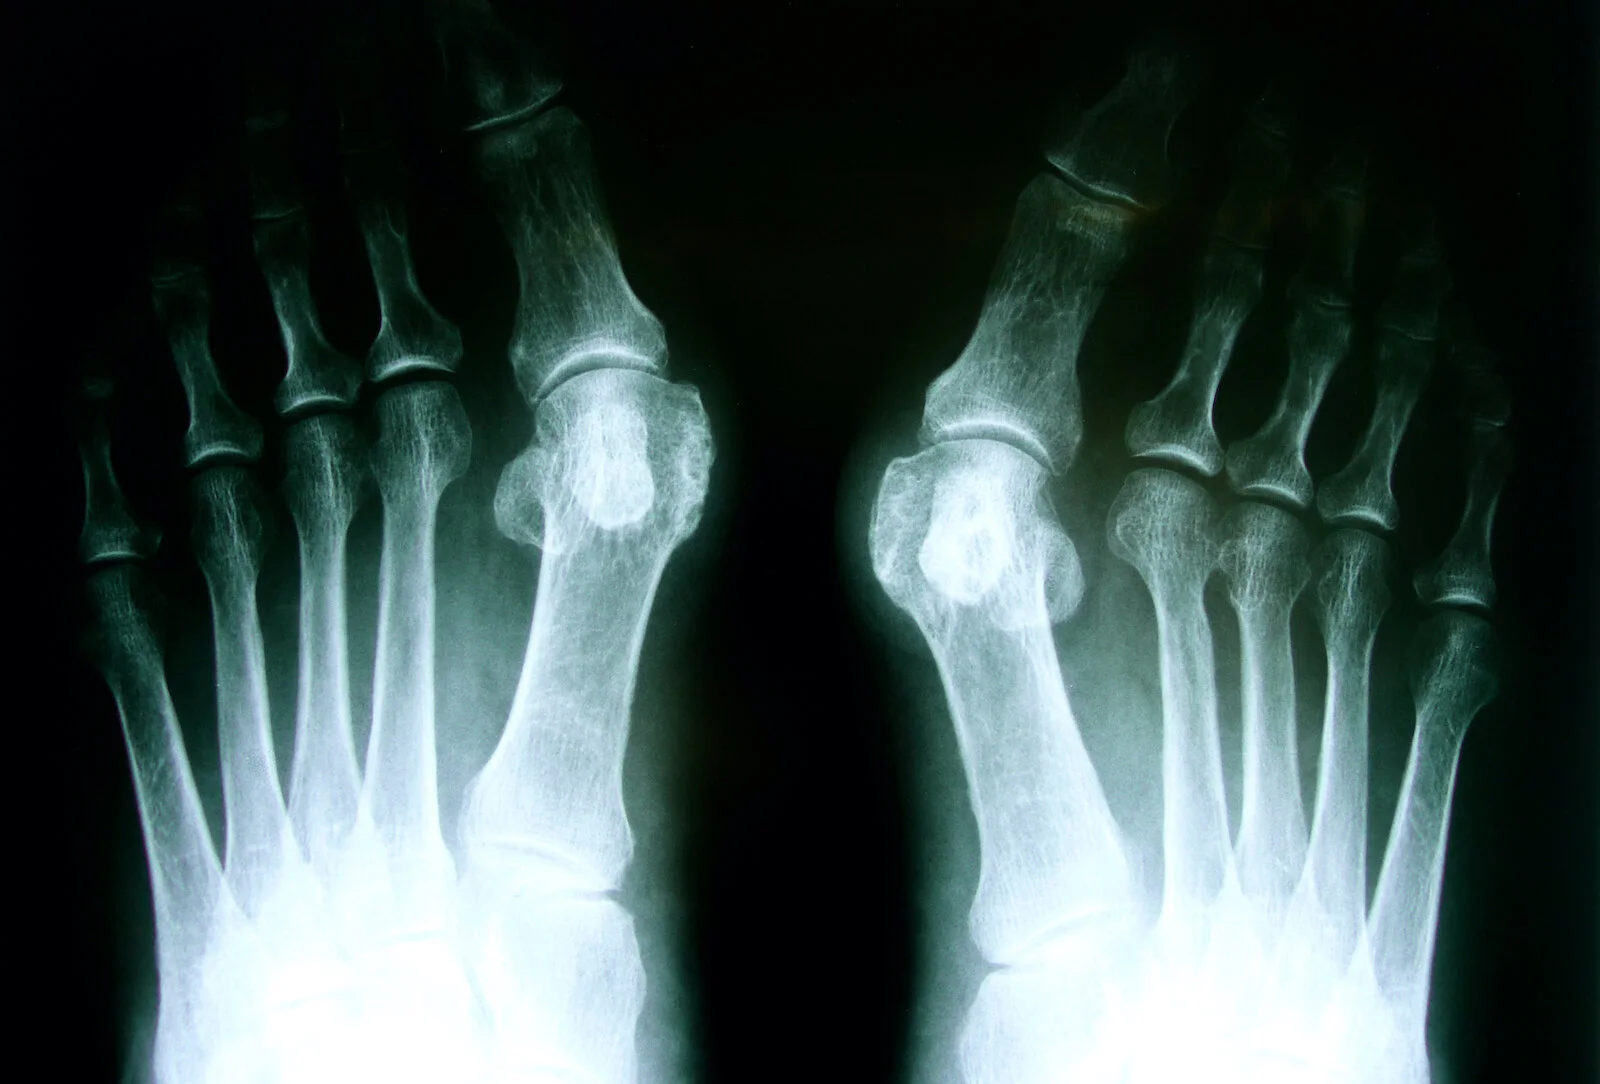

Bunion surgery recovery: An X-ray of feet

The twenty-four hours of the surgery or a few days before, a medico will bank check your vital signs to make sure you're healthy enough to undergo the surgery. The doctor may take x-rays or perform an electrocardiogram to evaluate your eye and lung function. They may too draw blood or inquire for a urine test to rule out any underlying medical conditions that may crusade complications.

Before getting bunion surgery, a md will take x-rays to determine the severity of your bunion. This will help inform the treatment plan and allow the doc to meliorate determine whether surgery is necessary. Depending on your ten-rays, a physician may recommend different types of bunion surgery. Hither are the unlike types of surgeries used to care for bunions.